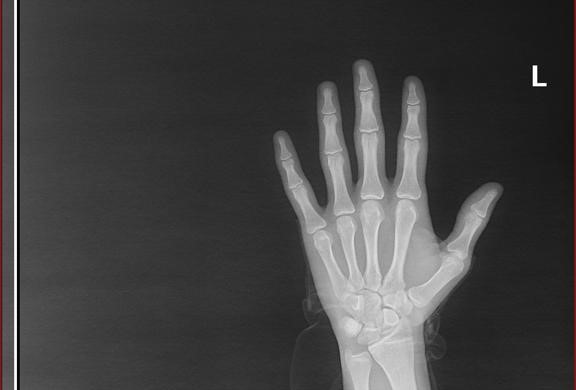

Herkese iyi akşamlar. 15 yıl 4 ay yaşamışım. Annem 153 cm babam 178 cm. Ben ise 168 cm ve 56 kiloyum. 5 gün önceki sol el röntgenimi aşağıda paylaştım. Bu konuda pek çok araştırma yaptım ama kayda değer bir sonuç bulamadım. Boyum en azından 175 cm olur mu? Amcalarım ve dedem uzunlar. İşin ehli hocalarım yardımcı olurlarsa çok memnun olurum.